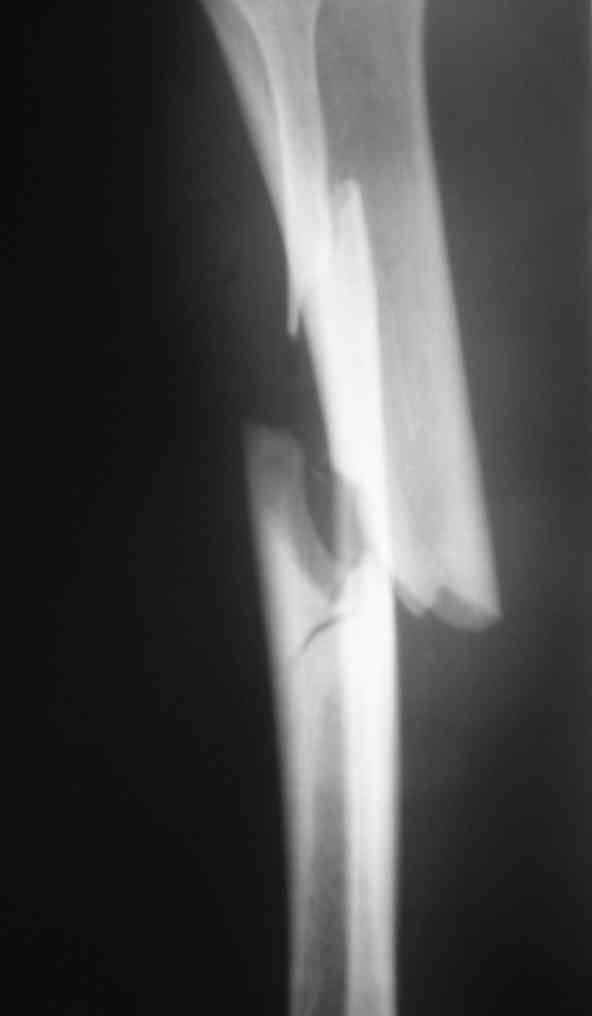

Вчера первый раз синтезировали голень гвоздем Fixion.

Спиральный оскольчатый перелом, ниже середины, у молодого парня. Сделали "классический" вариант гвоздя, который еще без винтов. Получилось все легко. Не торопясь, сделали операцию минут за 20. См. фото.

В отношении ранней нагрузки при спиральных переломах лучше не торопиться. По данному случаю необходимо достигнуть исчезновения щели между штифтом и внутреним кортексом по Rg. А так картинка прекрасная - и длина сегмента и репозиция. Можно поздравить, коллега!